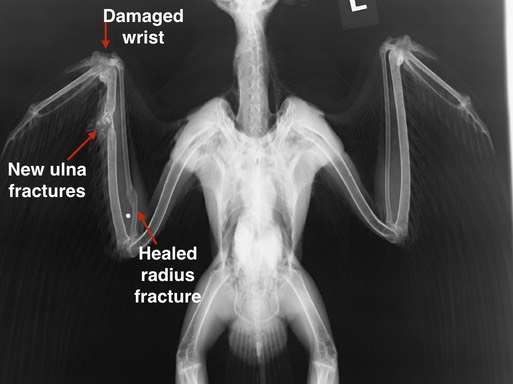

19-557 was a young hawk, not yet a year old, who had managed to recover from a fractured radius. Then someone shot him. The damage was too extensive to repair and he was euthanized.

19-558 had recovered from a radius fracture after being shot. Then he was shot a second time fracturing his ulna and damaging his elbow and wrist. The prognosis for having a functional wing was very poor and the hawk was euthanized.